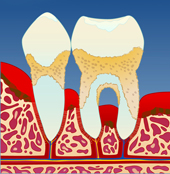

figur I figur II figur III figur IV

Dersom belegget ikke fjernes, vil det over tid forkalkes og bli hardt. Det er dette vi kaller tannstein. Tannstein forsterker betennelsen som fører til at benet rundt tennene brytes ned (II). På denne måten vil tannstein og bakteriebelegg kunne strekke seg stadig lenger ned langs rotoverflaten (III). Bentapet kan over tid bli så omfattende at tenner løsner og eventuelt må fjernes (IV).